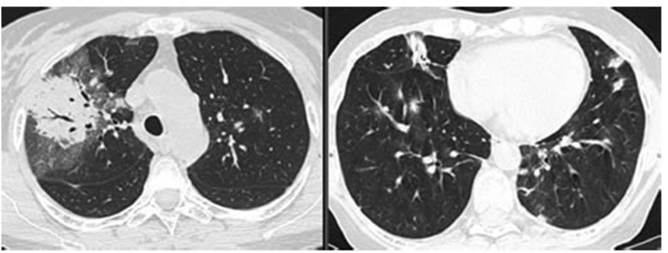

Se solicita nuevamente TC 21/01/2022 (Figura 2):

Se observa reducción de tamaño de los infiltrados bibasales con aparición de otros nuevos infiltrados

en lóbulos superiores. Consolidación con broncograÂma

aéreo rodeada de “vidrio esmerilado” con engrosamiento de septos interlobulillares en el segmento anterior y posterior del

lóbulo superior derecho.